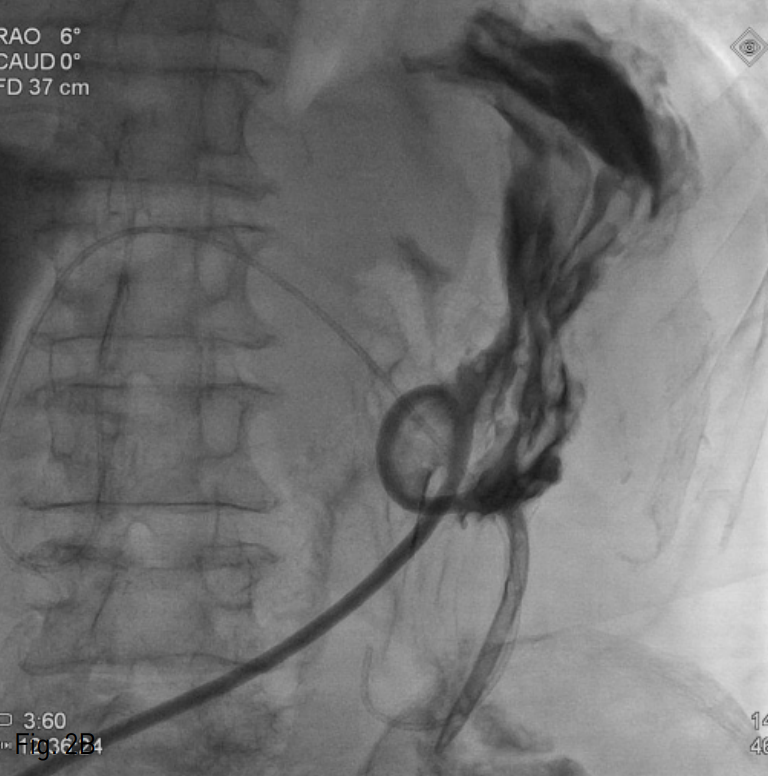

Fig. 2

A. Fluoroscopic image shows retrograde passage of air insufflation catheter through percutaneous transhepatic gallbladder drainage to the stomach.

B. Final fluoroscopic image shows adequate placement of percutaneous radiologic gastrostomy tube with contrast filled stomach.

먼저 위 공기 팽창을 위해 Gastro-tube를 삽입하려고 시도하였으나 하인두 이하로 진입이 불가능 하였다. 초기 투시경 사진상 장시간의 금식으로 인해 위장은 허탈되어 있고, 횡행 결장의 공기 음영이 상복부에 위치하여, 위 공기 팽창이 필수적이라고 생각되었다. 먼저 술자의 이전 경험에 비추어 22G Chiba needle과 hairwire (A&A medical, Seoul, Korea)를 이용하여 우측 간내 담관을 천자하여 위내 공기 팽창용 catheter를 삽입하려 하였으나, 환자의 척추 후만증으로 인한 자세불안정과 늘어나지 않은 상태의 정상 우측 담관 구조로 인해 천자에 실패하였다. 그래서 초음파 유도하에 담낭을 천자하여, 5 Fr angio-sheath (Terumo, Tokyo, Japan)를 설치하였다. Sheath를 통하여, 다시 0.035 inch guide wire (Terumo, Tokyo, Japan)와 5Fr Cobra catheter (Cook, Bloomington, IN,USA)를 이용하여 후향적으로 위 분문부에 진입하였다 (Fig.2A). 실내 공기 500cc를 주입하여 위를 팽창시킨 후 약간의 조영제를 주입하여 위벽 주름을 조영하였다. 다시 복벽을 리도카인을 이용하여 국소 마취한 후, 복직근 외연부 라인에서 적당한 위 분문부를 위저방향으로 22G Chiba needle과 hair wire (A&A medical, Seoul, Korea)를 이용하여 위 주름이 밀리는 것을 관찰하며 천자하였다. 다시 4 Fr sheath (Cook, Bloomington, IN, USA)를 거치한 후 T자형 고정 장치를 삽입하였고, 통상적인 위창냄술의 방법대로 경로를 확장하였다. 12 Fr 위창냄술 튜브 (Cook, Bloomington, IN, USA)를 삽입하고, 조영제를 주입하여 튜브의 위치와 기능, 복강 내로 유출이 있는지를 확인하였다 (Fig. 2B). 마지막으로 T자형 고정장치와 튜브를 피부에 고정하였고, 이후 담낭 내에 8.5 Fr Pigtail catheter (Cook, Bloomington,IN,USA)를 거치 한 후 시술을 종료 하였다.